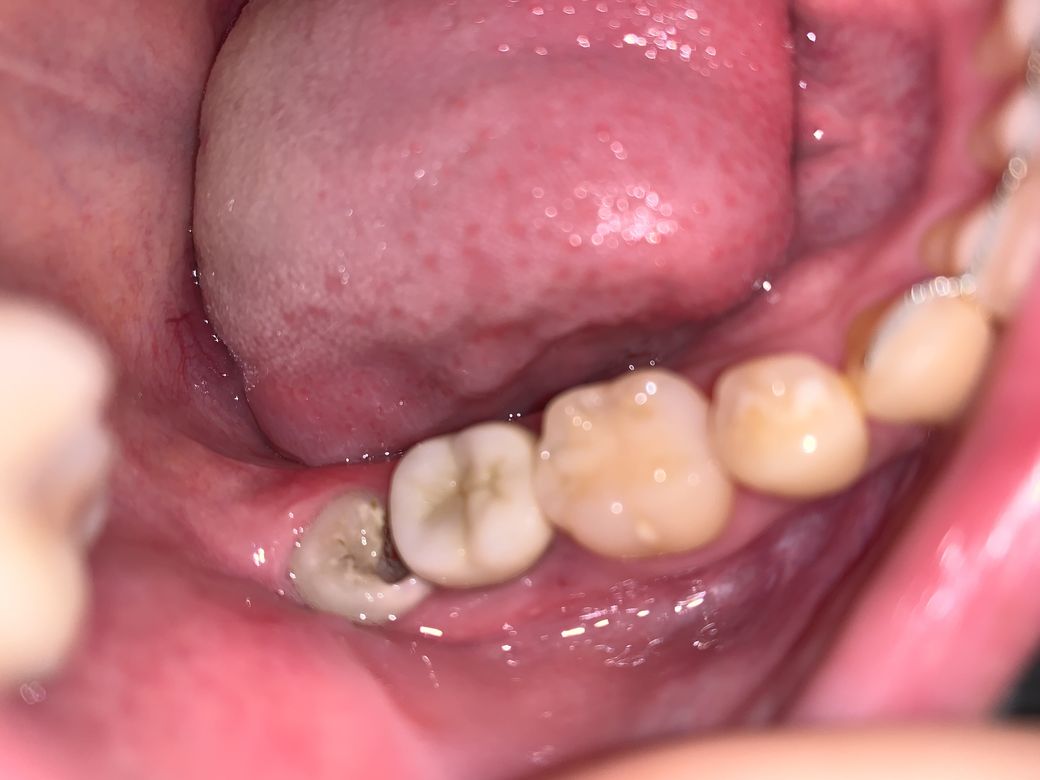

사랑니가 썩었는데 이런 경우 치근흡수 가능성이 있나요?

교정 후 갑자기 사랑니가 자랐습니다

위치는 오른쪽 하악 입니다 , 세달 전 만 해도 멀쩡했는데 어느날 혀로 더듬어 보니 구멍이 뚫려 있더군요

사랑니 나는 동안은 아파서 왼쪽으로만 씹었기에 이지경 까지 된지는 몰랐습니다, 양치시에도 아프진 않았습니다

제가 궁금한 것은 사랑니 앞 어금니가 썩으면 뽑고 임플란트 해야 할 수도 있다고 들었는데 불행중 다행인지 신경치료 한 치아여서 외관상 썩은 부분은 보이지 않으나

치근흡수(?) 그게됐을까봐 두렵습니다

사진으로 봤을때 가능성이 있을까요 ?

사진이 돌아간점 양해 부탁 드립니다.

• 1번 째 사진

사랑니에 심한 충치가 발생한 상태로, 사랑니 앞 어금니의 옆면에도 충치가 있을 가능성이 있습니다.

하지만 해당 치아에 크라운이 씌워진 상태로, 크라운이 없는 상태 보다는 그 가능성이 낮아질 수는 있으나, 여전히 크라운 하방으로 충치가 발생했을 가능성은 있습니다.

하지만 구강 사진만으로는 충치 여부를 알 수 없고, 방사선 사진을 통해 충치발생 여부를 판단할 수 있으며, 가장 정확한 것은 사랑니를 발치한 후에 앞 치아의 뒷면을 살펴봄으로써 충치 여부를 정확하게 판단할 수 있습니다.

사랑니충치가 심한것으로 보입니다.

사랑니는 발치해주시는게 좋습니다.

사랑니로 인해 간혹 앞의 치아에 충치가 심하게 생기거나, 치근이 흡수되는경우도 있지만, 이 사진만으로는 알수없습니다.

정확한것은 치과에서 방사선사진을 찍어서 확인해보시기 바랍니다. 감사합니다.